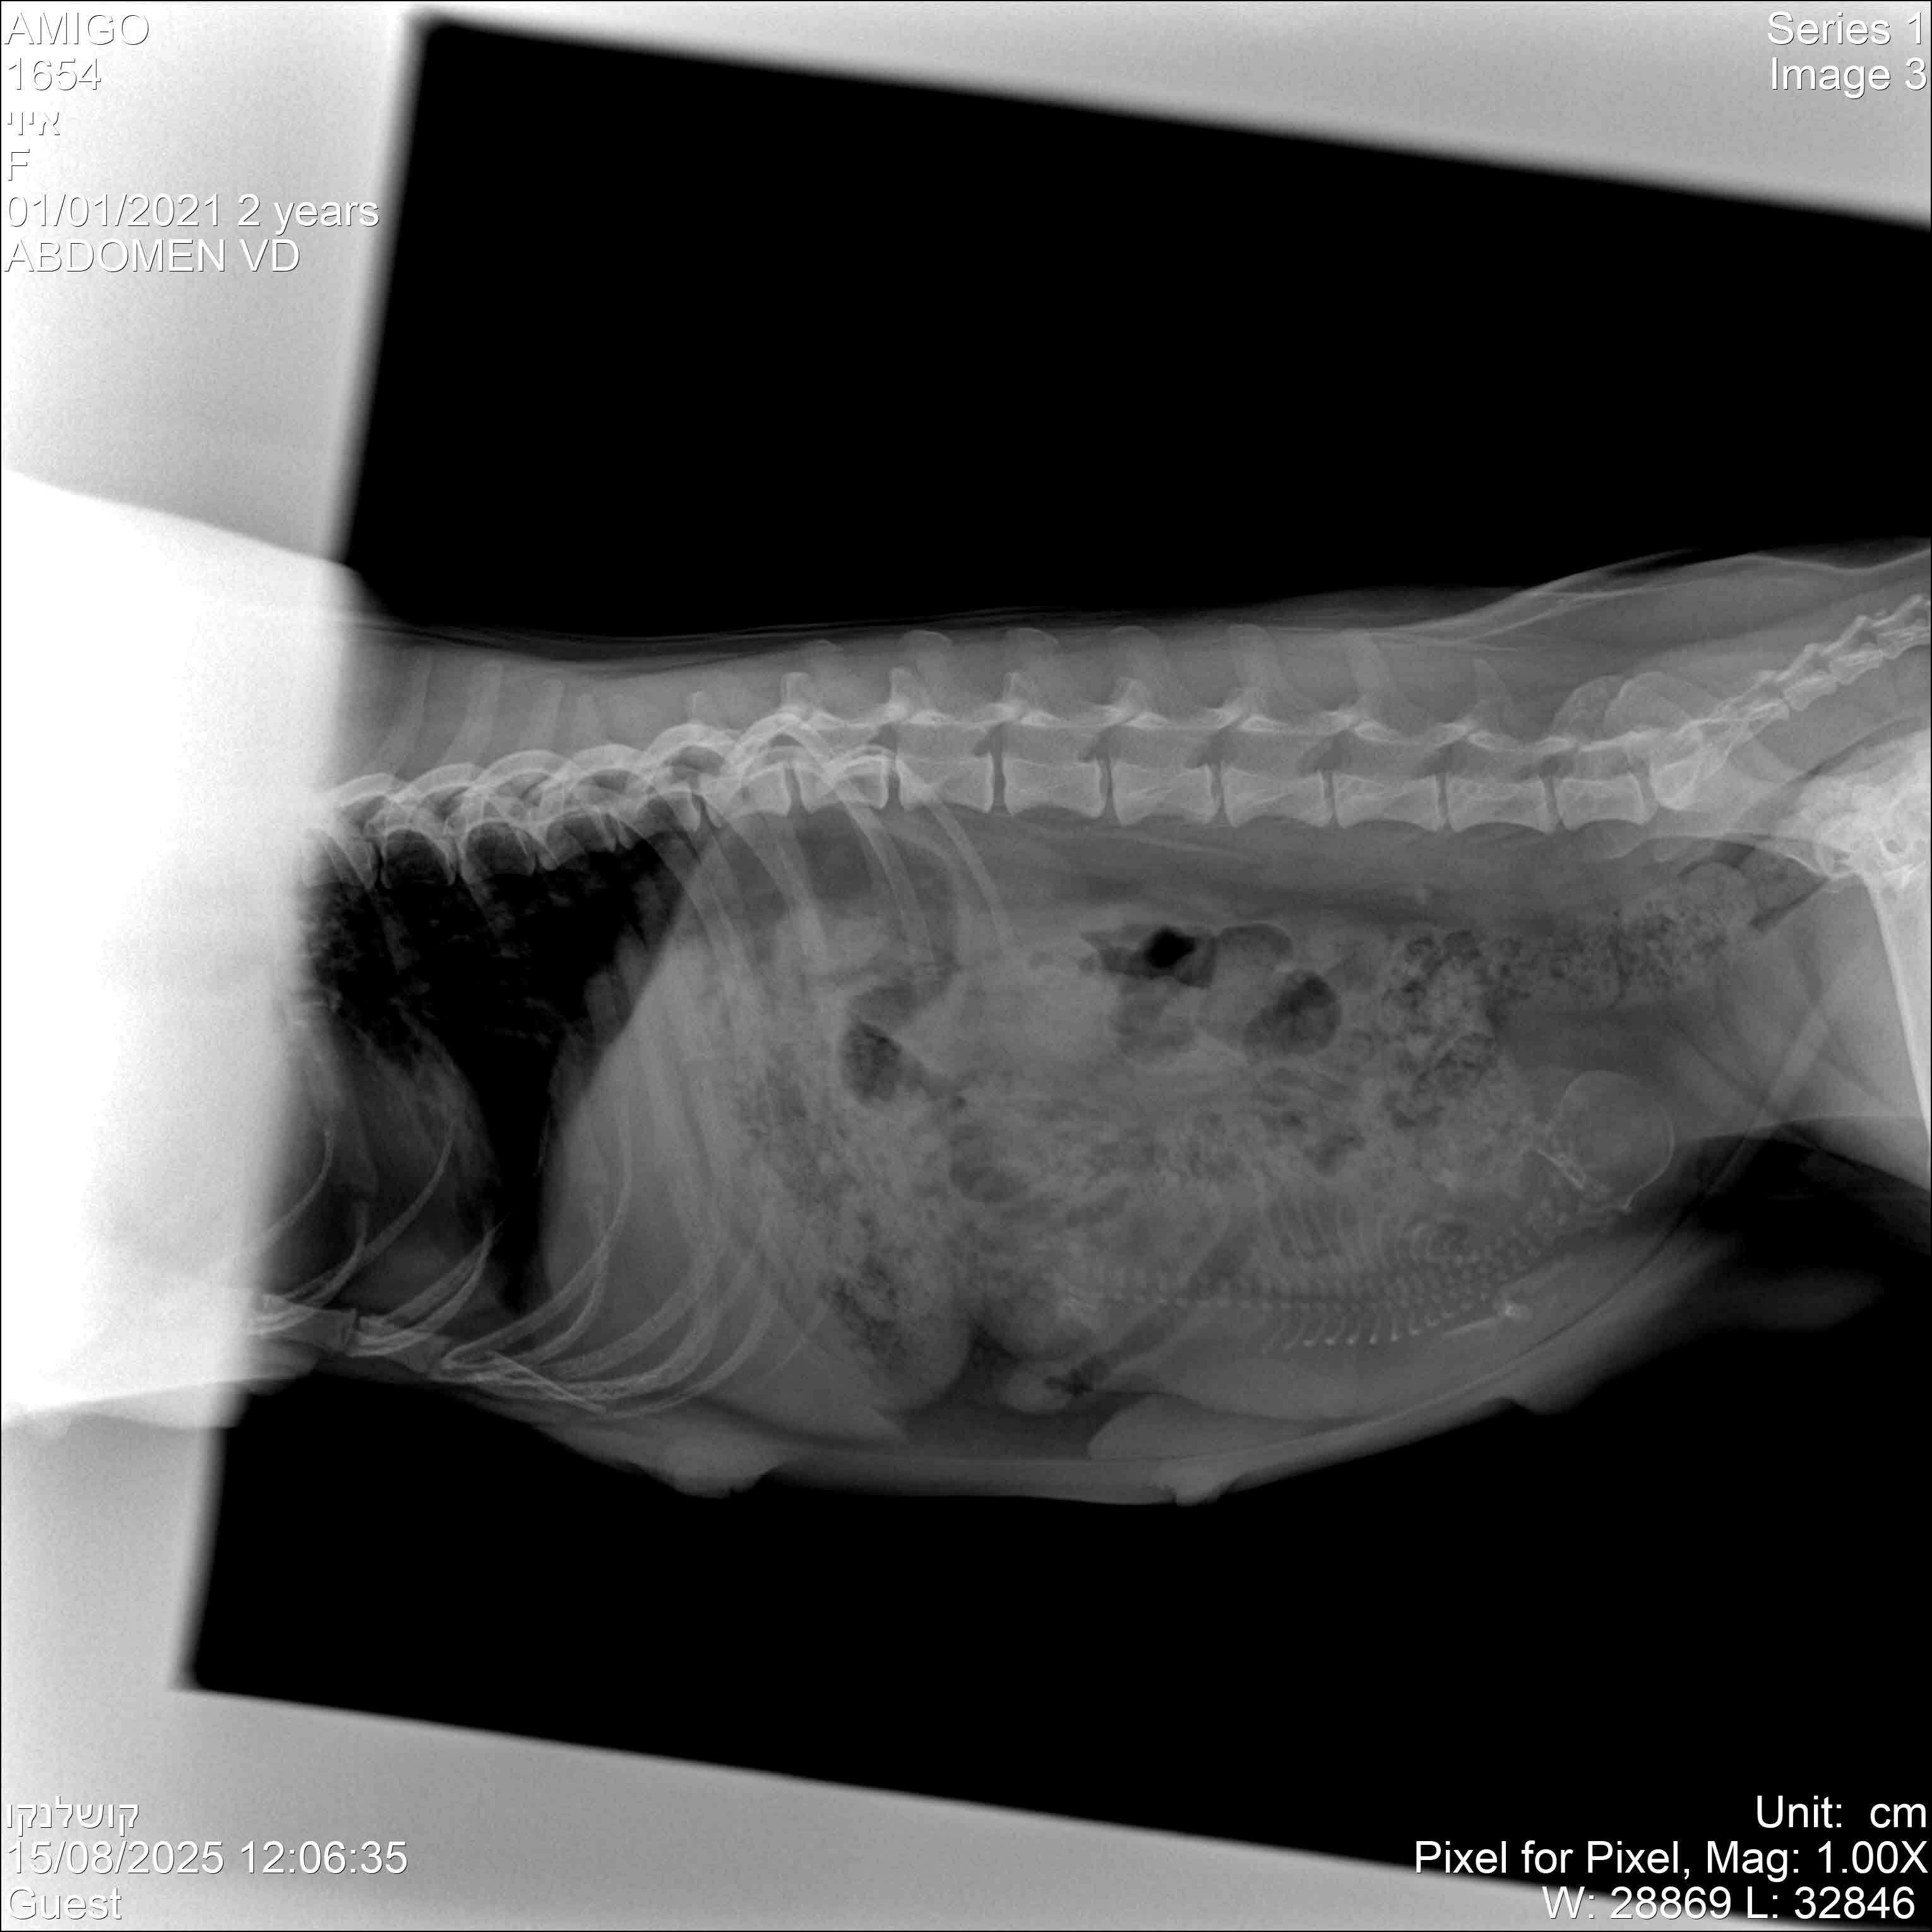

А 15 августа, на 55 день с вязки, мы поехали делать рентген - там можно посчитать щенков гораздо точнее (по головам или позвоночным столбам).

Ну вот... можете судить сами: